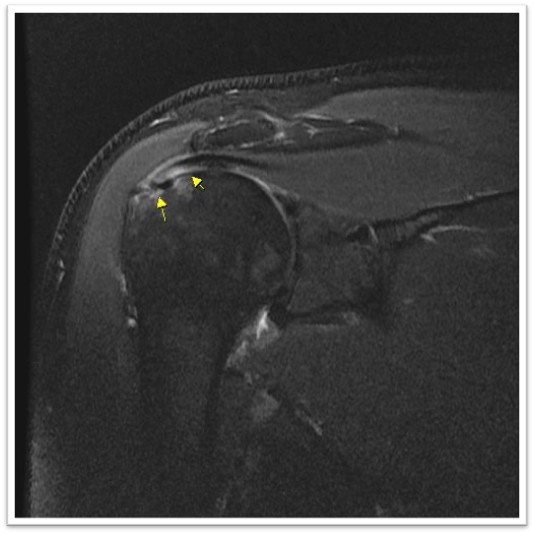

MRI와 초음파를 다시 검토했습니다.

회전근개 극상건의 관절면측(articular-side) 부분파열.

관절면측(articular-side) 파열은 회전근개의 아래쪽, 즉 관절에 면한 부분이 손상된 것입니다.

3. 방치하면 전층파열로 진행합니다

*Journal of Shoulder and Elbow Surgery*에 발표된 연구에 따르면, 관절면측 부분파열 환자의 상당수가 시간이 지나면서 전층파열로 진행합니다.¹

특히 파열이 50% 이상인 경우, 진행 위험이 더 높습니다.